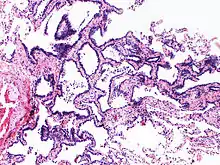

Image histologique de l'hyperplasie adénomateuse atypique.

L'hyperplasie adénomateuse atypique (HAA) est une lésion hyperplasique des pneumocytes bordant les alvéoles pulmonaires et présentant des anomalies cytonucléaires discrètes[1]. Ce terme est préconisé par l'Organisation mondiale de la santé dans sa classification des tumeurs de 2011, puis maintenu et précisé dans les versions de 2015 et 2021. Il caractérise une lésion glandulaire précurseur (précédemment dite lésion préinvasive) de très petite taille[2],[3].

Cette anomalie, de petite taille, inférieure ou égale à mm[3], est une dysplasie, précancéreuse, précurseur de l'adénocarcinome pulmonaire in situ[4]. Le terme de carcinome bronchioloalvéolaire, autrefois employé pour décrire cette lésion est désormais abandonné[4].